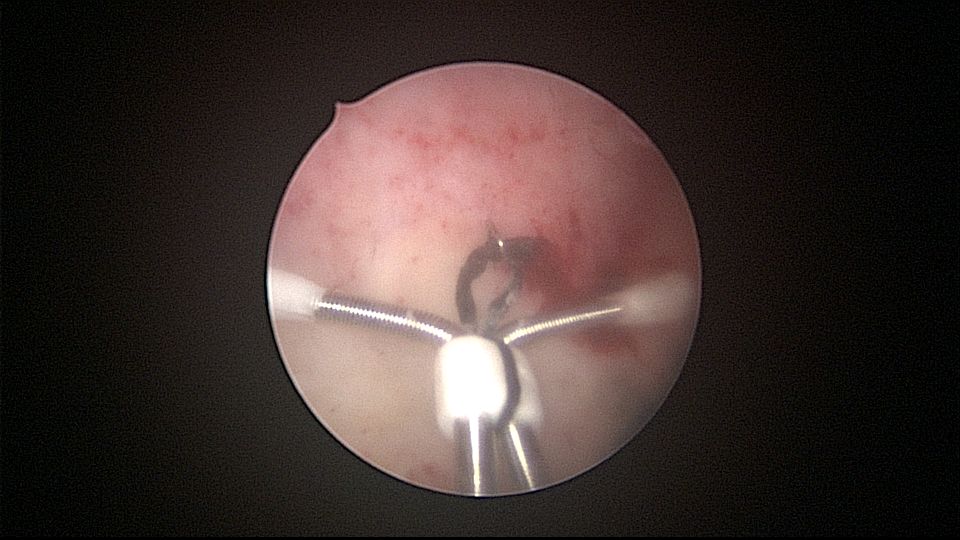

患者32岁,G6P2,顺产2次。2025年3月,停经56天,计划外妊娠,要求终止妊娠并放置节育环,考虑终止妊娠后宫腔大,担心环移位或脱落,要求固定节育环。γ环没有尾丝,用4号丝线连接环及不锈钢挂钩,将挂钩插入宫底肌层固定,异物钳原位固定曼月乐,退出宫腔镜,结束手术。术后患者未回院复查节育环位置。